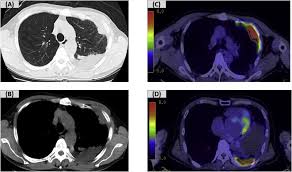

Mesothelioma Lung Cancer Ct And Pet Stock Image C021 3587 Science Photo Library from media.sciencephoto.com 9 malignant mesothelioma has been … Learn about symptoms, treatment, and the outlook for people with kidney cancer here. 20.02.2019 · can mesothelioma cause kidney failure? 14.01.2020 · find mesothelioma kidney cancer information. Ji and his colleagues say further study is needed to fully understand the possible connection between mesothelioma, bladder cancer, and kidney cancer. In december last year i was diagnosed with kidney cancer. Mesothelioma is an especially rare and aggressive type of cancer, caused almost exclusively by exposure to asbestos. Mesothelioma is a rare form of …